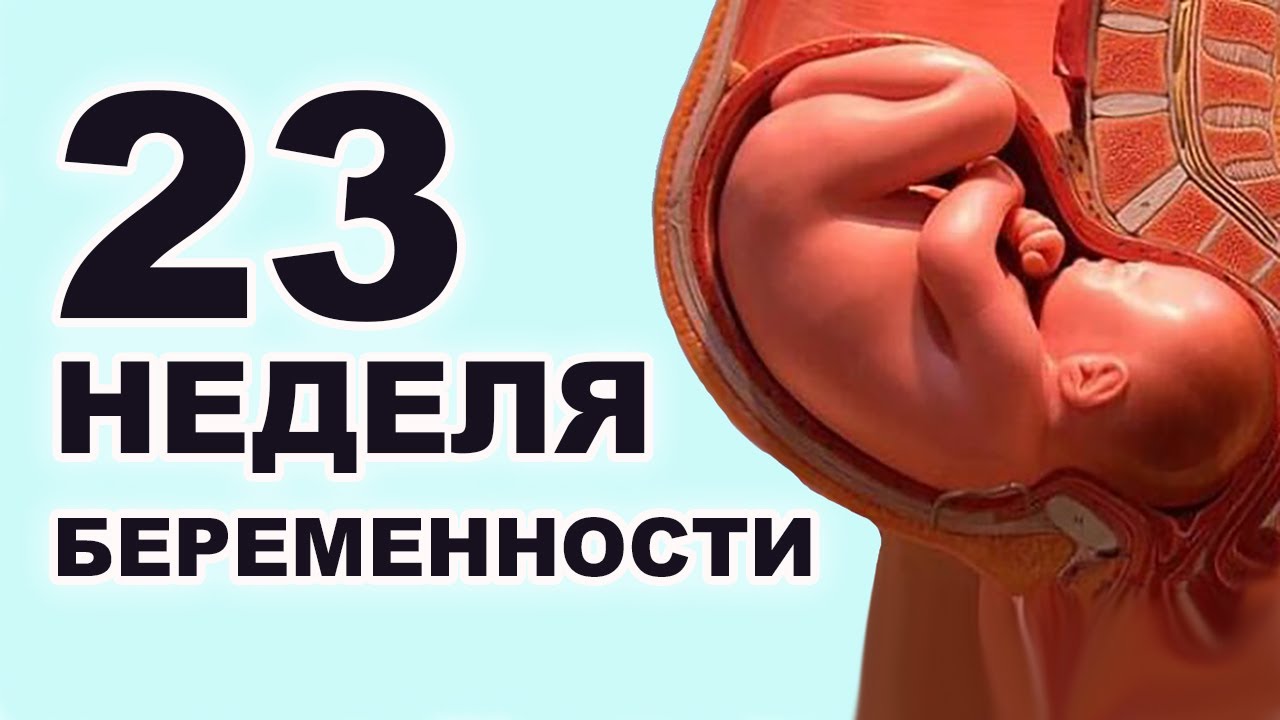

За 23 недели беременности ваш вес увеличился на 5-7 кг.

На 23 неделе малыш продолжает накапливать подкожно-жировую клетчатку, он округляется, принимает более привычный для глаза вид, однако, пока он все еще имеет вид маленького сморщенного красного человечка. За счет накопившихся пигментов, кожа перестает быть прозрачной.

Головной мозг малыша увеличился, нервные связи в нем налаживаются, что требует от мамы обязательных прогулок на свежем воздухе. О нехватке кислорода малыш предупредит маму усиленными толчками. С помощью специальных приборов, возможно зарегистрировать активность головного мозга. Малыш начинает видеть сны.

Глаза плода открыты, он различает свет и темноту, реагирует на них изменением поведения. Хорошо он различает и звуки, изменяя свое поведение при резких шумах.

Пищеварительная система готова выполнять свои функции, ребенок постоянно заглатывает околоплодные воды, жидкая часть которых расщепляется на сахар и воду и всасывается в кишечнике, а попавшие с водами чешуйки и пушковые волосы формируют меконий, который в норме выводится только после родов.

На этом сроке, если малыш не очень стеснительный, можно определить, кто в скором времени появится на свет. Половые признаки дифференцируются отчетливо.

К23 неделе матка женщины увеличиваетсяв размерах и поднимается на 4 см надпупком. Женский орган уже давит надиафрагму, поэтому в это время у беременныхмогут появиться проблемы с дыханием.Сложно сделать глубокий вдох, дыханиестановится поверхностным и прерывистым.

Далее разберемся, что происходит с малышом в описываемый период беременности. Интенсивно идет развитие головного мозга, у плода в 23 недели мозг весит в 10 раз больше, чем три месяца назад, и в 5 раз больше, чем две недели назад.

Кроме того, нужно стараться избегать стрессовых ситуаций, ведь переживания мамы могут стать причиной гипоксии плода. Малыш на 23 неделе беременности уже достаточно хорошо развит:

- у него уже полноценная пищеварительная система;

- функционирует поджелудочная железа, производящая инсулин;

- плод постоянно тренирует свои лёгкие, готовясь дышать самостоятельно:

- «включается» в работу селезенка;

- пальцы на всех четырех конечностях становятся длиннее;

- ноготки становятся прочнее;

- на этом сроке могут начать открываться глаза, и ваш ребенок скоро начнет различать свет;

- постепенно накапливается жировая ткань и, благодаря этому, кожа выглядит все более гладкой;

- вес плода в это время составляет около половины килограмма, а его рост приближается к 30 см. Если вы носите двойню, то дети могут иметь разный вес. Практически всегда одна двойняшка более крупная, разница в весе между детьми может составлять 50-60 граммов.

К двадцать третьей неделе вес ребенка составляет около 520 грамм, рост 28-30 сантиметров.

К 23 неделе с Вашим ребенком произойдут также следующие изменения:

- Начинается нарост жира. Несмотря на это, пока что Ваш малыш выглядит сморщенным и красным. Причина в том, что кожный покров формируется намного быстрее, чем под ним успевают оформиться достаточные жировые отложения. Именно из-за этого кожа ребенка немного обвислая. Краснота, в свою очередь, является следствием накопления пигментов в коже. Они делают ее не такой прозрачной;

- Плод проявляет больше активности. Как говорилось выше, с каждой неделей Ваш малыш становится все более энергичным, хотя и толкается еще очень мягко. При эндоскопии плода на таком сроке можно заметить, как ребенок толкается в водную оболочку и хватается ручками за пуповину;

- Достаточно развита пищеварительная система. Ребенок продолжает заглатывать небольшое количество амниотической жидкости. На 23 неделе малыш может проглотить ее до 500 мл. Выводит он ее из организма в виде мочи. Так как в околоплодных водах содержатся чешуйки эпидермиса, частички защитной смазки, пушковые волосы, то вместе с водами ребенок периодически заглатывает и их. Жидкая часть амниотической жидкости всасывается в кровь, а в кишечнике остается вещество темно-оливкового цвета, которое называется меконий. Меконий формируется со второй половины, но выделяется в норме только после появления на свет;

- Развивается центральная нервная система малыша. На таком сроке с помощью приборов можно уже зарегистрировать активность головного мозга, которая схожа с таковой у родившихся детей и даже у взрослых. Также, на 23 неделе ребенок может видеть сны;

- Глаза уже открылись. Теперь малыш видит свет и темноту и может на них реагировать. Слышит ребенок уже очень хорошо, он реагирует на разнообразные звуки, усиливает свою активность при резких шумах и успокаивается при ласковом разговоре и поглаживании животика.

На 23-й неделе беременности рост малыша в утробе достигает 29-30 см, а вес – 500 г. Тело малыша к этому сроку уже полностью сформировано, кожа ещё обильно покрыта волосками, а подкожный жир только недавно начал формироваться. Малыш уже активно двигается, сообщая об этом маме толчками, и сосёт палец.

Пищеварительная система малыша на 23-й неделе полностью сформирована. Ребенок не только заглатывает амниотическую жидкость, но и синтезирует из неё воду и сахар. Уже несколько недель ребенок ощущает вкус.

К 23-й неделе у малыша начинает работать селезенка, отвечающая за формирование кровяных клеток.

В середине 5-го месяца малыш уже различает звуки, чувствует тепло и реагирует на свет. Ученые склоняются к мнению, что на этом сроке кроха уже видит сны.

Мозг во втором семестре активно развивается, сейчас он весит уже около 100 г (20% от общего веса тела). Именно поэтому, будущая мама обязана обеспечить малышу лучшие условия: как можно больше свежего воздуха, правильный рацион и никаких вредных продуктов.